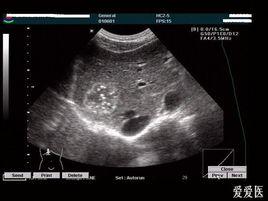

· 糞便漂浮(可見蟲卵)(圖1)